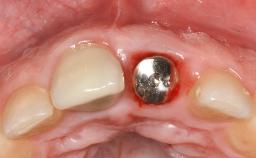

Occlusal Load—a Factor for Implant Failure?

In this case, Nicola Zitzmann describes the sudden loss of a previously well-osseointegrated implant that had been in healthy function for 5 years. The case includes recommendations for occlusion and function of implant restorations. A 74-year-old patient had received implant-fixed dental prostheses in the maxilla in 2008, and in the right mandible three years later. His tooth loss was mainly related to recurrent caries associated with hyposalivation as a potential side effect of his cholesterol-lowering medication.